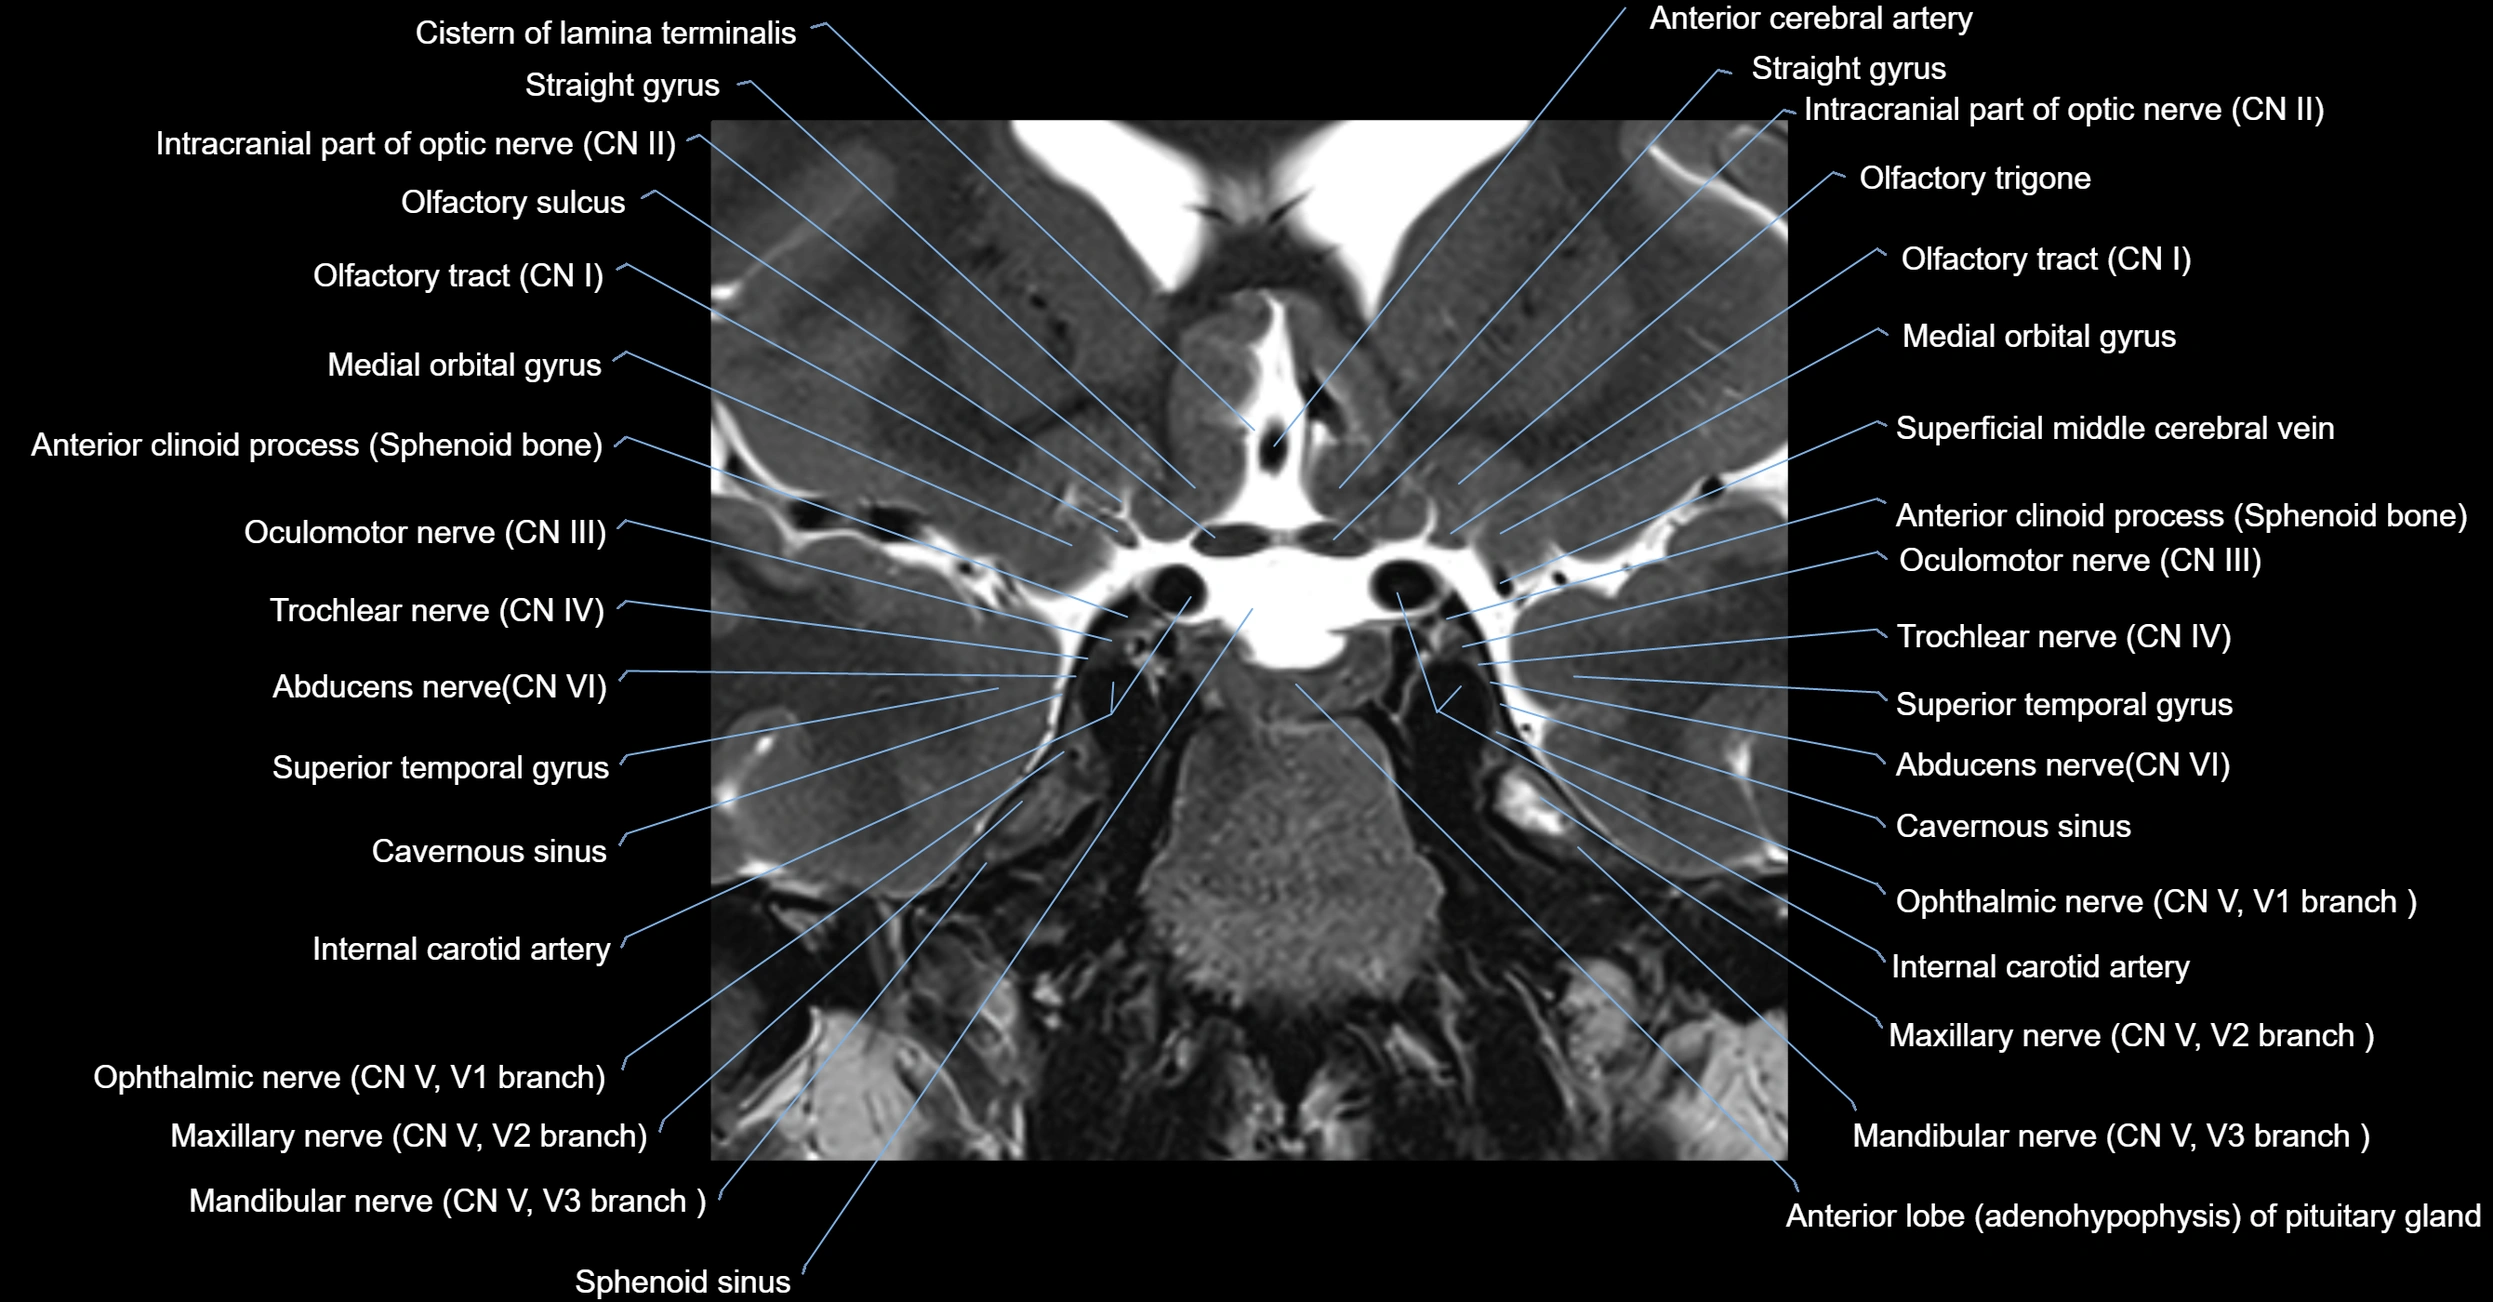

MRI Appearance

The abducens nerve is a small, thin, linear structure

Best visualized on high-resolution T2-weighted 3D MRI sequences (e.g., FIESTA or CISS)

Seen as a hypointense (dark) line running from the brainstem at the pontomedullary junction, traversing the prepontine cistern, and entering Dorello’s canal under the petrosphenoidal ligament, then into the cavernous sinus, and finally the orbit

May be challenging to visualize in standard MRI due to its small size

Pathology may be inferred by absence, displacement, or enhancement of the nerve

MRI images